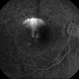

- CSCR mushroom cloud

- CSCR subfoveal leak

Topcon 50X with Merge capture station - Description

- Late transit FA of a large active sub-foveal CSCR leak. You may view this pair in stereo to appreciate the plume of leakage within this large serous RD of the macula. This patient presented with a BCVA of 20/200 and fluorescein and historic evidence of prior episodes of leakage. After discussion of known treatment options including observation, he elected to be treated initially with oral rifampin and BCVA improved to 20/40 with persistent metamorphosis and a shallower persistent macular detachment over several visits. Rifampin was discontinued and he then received sub-threshold micro-pulse laser photocoagulation with an 810 diode which resulted in the patient reporting full restoration of his vision subjectively within a month. He failed to keep his follow-up appointment.